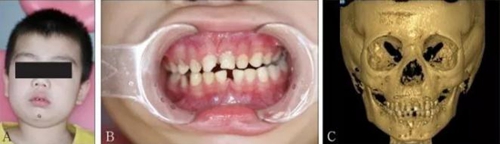

頜面部上下頜骨、顴骨及顴弓骨折、骨折片移位壓迫咀嚼肌群和下頜骨喙突,影響下頜骨的活動而造成張口受限[10-12](圖 9、10)。

A:患者面像;B:口內像;C:三維成像;D:全景片;E:冠狀位。

圖 9 面部外傷